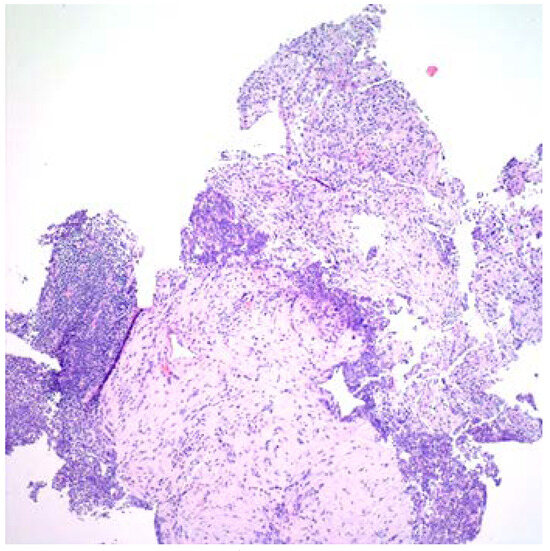

Introduction: Fusobacterium nucleatum is a Gram-negative, obligate anaerobic bacterium which predominantly resides within the oral cavity and causes acute abscesses and venous thrombosis, primarily in the head and neck region, but could have unique clinical presentations in different anatomical regions of the body. Case report: We present a case of subacute liver abscesses extending to the lung. The histopathological examination showed extensive necrosis and fibrosis. The chronic course, extensive fibrosis and extension across the anatomic barriers were suggestive of actinomycosis. two sets of blood cultures grew Fusobacterium nucleatum, only 16s rRNA analysis of the liver tissue and pleural fluid revealed F. nucleatum DNA without other organisms. The clinical and pathological features of our case illustrate that F. nucleatum may mimic actinomycosis. Conclusions: This case illustrates that F. nucleatum should be considered in patients with subacute infections with extensive fibrosis that crosses anatomic barriers, mimicking actinomycosis. Full article